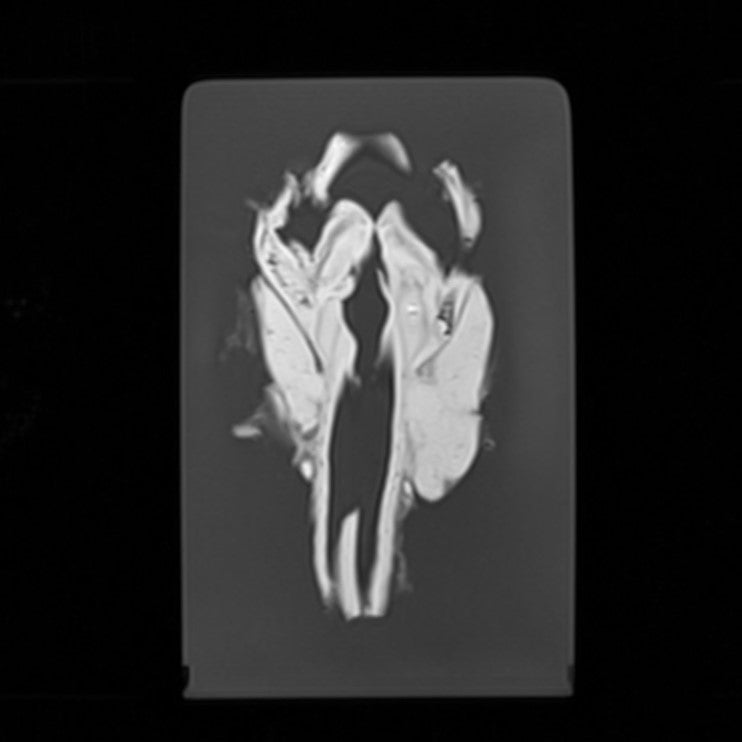

Thyroid - Papillary Carcinoma

Radiopath – Thyroid